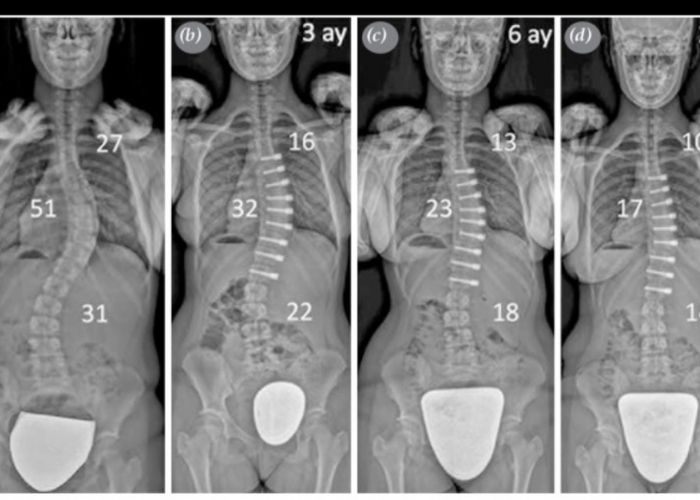

Multidisipliner Skolyoz Cerrahisinde VERTEBRAL Gövde Cerrahilerinin toraks bölümü Videotorakoskopik olarak tarafımca gerçekleştirilmektedir.